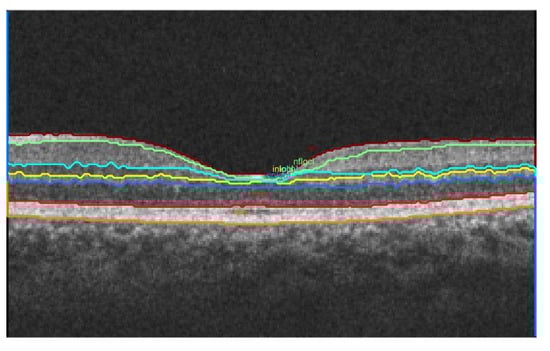

3.1. Retinal Layer Segmentation and Thickness Computation

| Layer | Segmented Intra-Retinal Layers (as Shown in Figure 1) | Thickness = Mean ± SD (in Microns) |

|---|---|---|

| 1 | RNFL + GCL | 25.02 ± 3.16 |

| 2 | IPL | 5.40 ± 2.79 |

| 3 | INL | 5.94 ± 1.10 |

| 4 | OPL | 8.45 ± 0.96 |

| 5 | ONL + IS | 16.24 ± 1.76 |

| 6 | OS + RPE | 12.67 ± 6.04 |